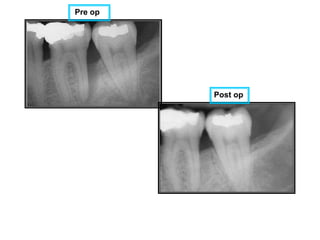

Pre op

Post op